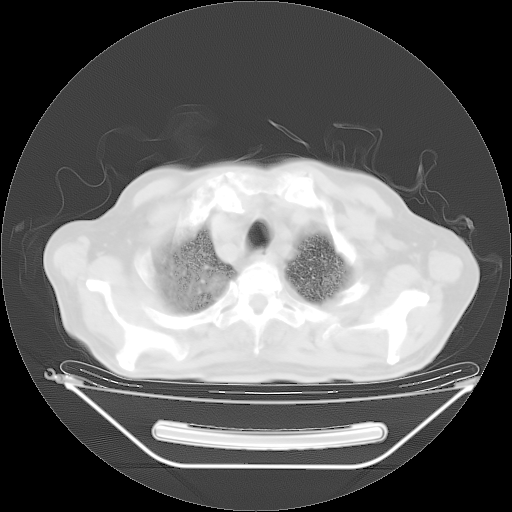

今天复查肺部CT,发现双肺广泛磨玻璃样改变。所以我把3月19日和5月9日相隔50天的肺部CT上传。请大家会诊。

2009年3月19日肺部CT片。

2009年3月19日肺部CT

5月9日肺部CT(在4月27日齐鲁医院肺部CT描述部分肺组织磨玻璃样改变,12天后肺组织广泛磨玻璃样改变)

大致读了系列胸部CT:纵隔窗无明显异常,肺窗:从4、27至今:主要是双肺中下野外带可见毛玻璃样改变,目前处于急性肺泡炎阶段,至于原因考虑1、结替组织或胶原血管性疾病所致?2、恶性疾病如恶组在肺部所致的表现或细支气管肺泡癌?3、药物或其它原因如肺蛋白沉着症所致肺泡炎目前不太可能?总之,明天就去请我院的呼吸科、感染科、血液科和临免专家会诊哈。